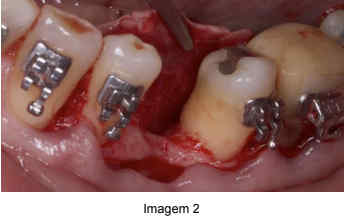

A incisão foi realizada na mucosa gengival, na região posterior da mandíbula, levando em consideração a localização da perda óssea. O descolamento do retalho mucoperióstico foi realizado com cuidado, utilizando um elevador periostal para preservar a vascularização e garantir a integridade do tecido ósseo. (Imagem 02)

Fonte: próprio autor